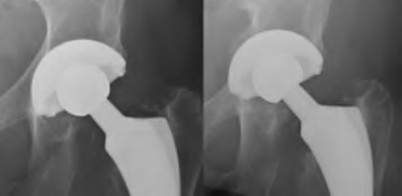

A 72-year-old female falls and sustains a periprosthetic femur fracture around her cementless total hip arthroplasty. Radiographs reveal a fracture extending just distal to the tip of the stem. The stem is radiographically loose, but there is excellent proximal and distal bone stock. According to the Vancouver classification, what is the fracture type and the recommended surgical treatment?

A 75-year-old female sustains a fall 5 years after a cementless THA. Radiographs show a periprosthetic femur fracture occurring around the stem tip. Intraoperative assessment reveals the stem remains firmly fixed in the metaphysis, and the proximal bone stock is adequate. According to the Vancouver classification, what is the fracture type and the standard recommended treatment?

A 45-year-old female with developmental dysplasia of the hip (DDH) presents for THA. Preoperative radiographs show the femoral head is subluxated, with 80% proximal migration relative to the height of the normal true acetabulum. Based on the Crowe classification, what type of dysplasia does she have?